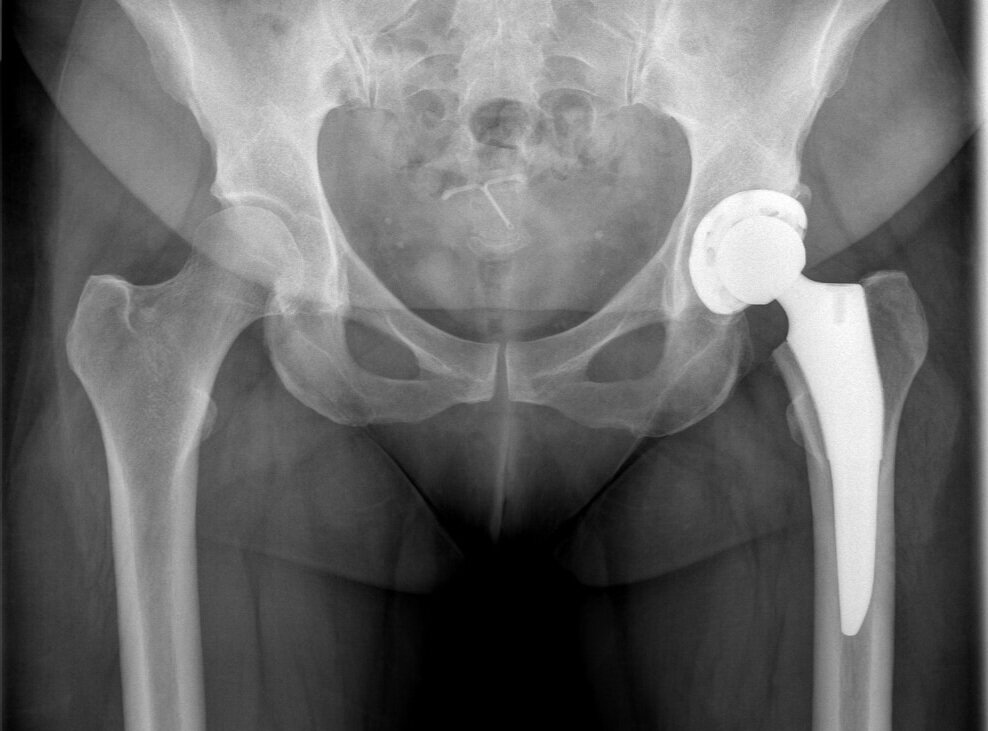

Total Hip Replacement

Total hip replacement (THR) is most commonly performed for painful hip osteoarthritis affecting quality of life on a daily basis. Section includes primary and revision THR.